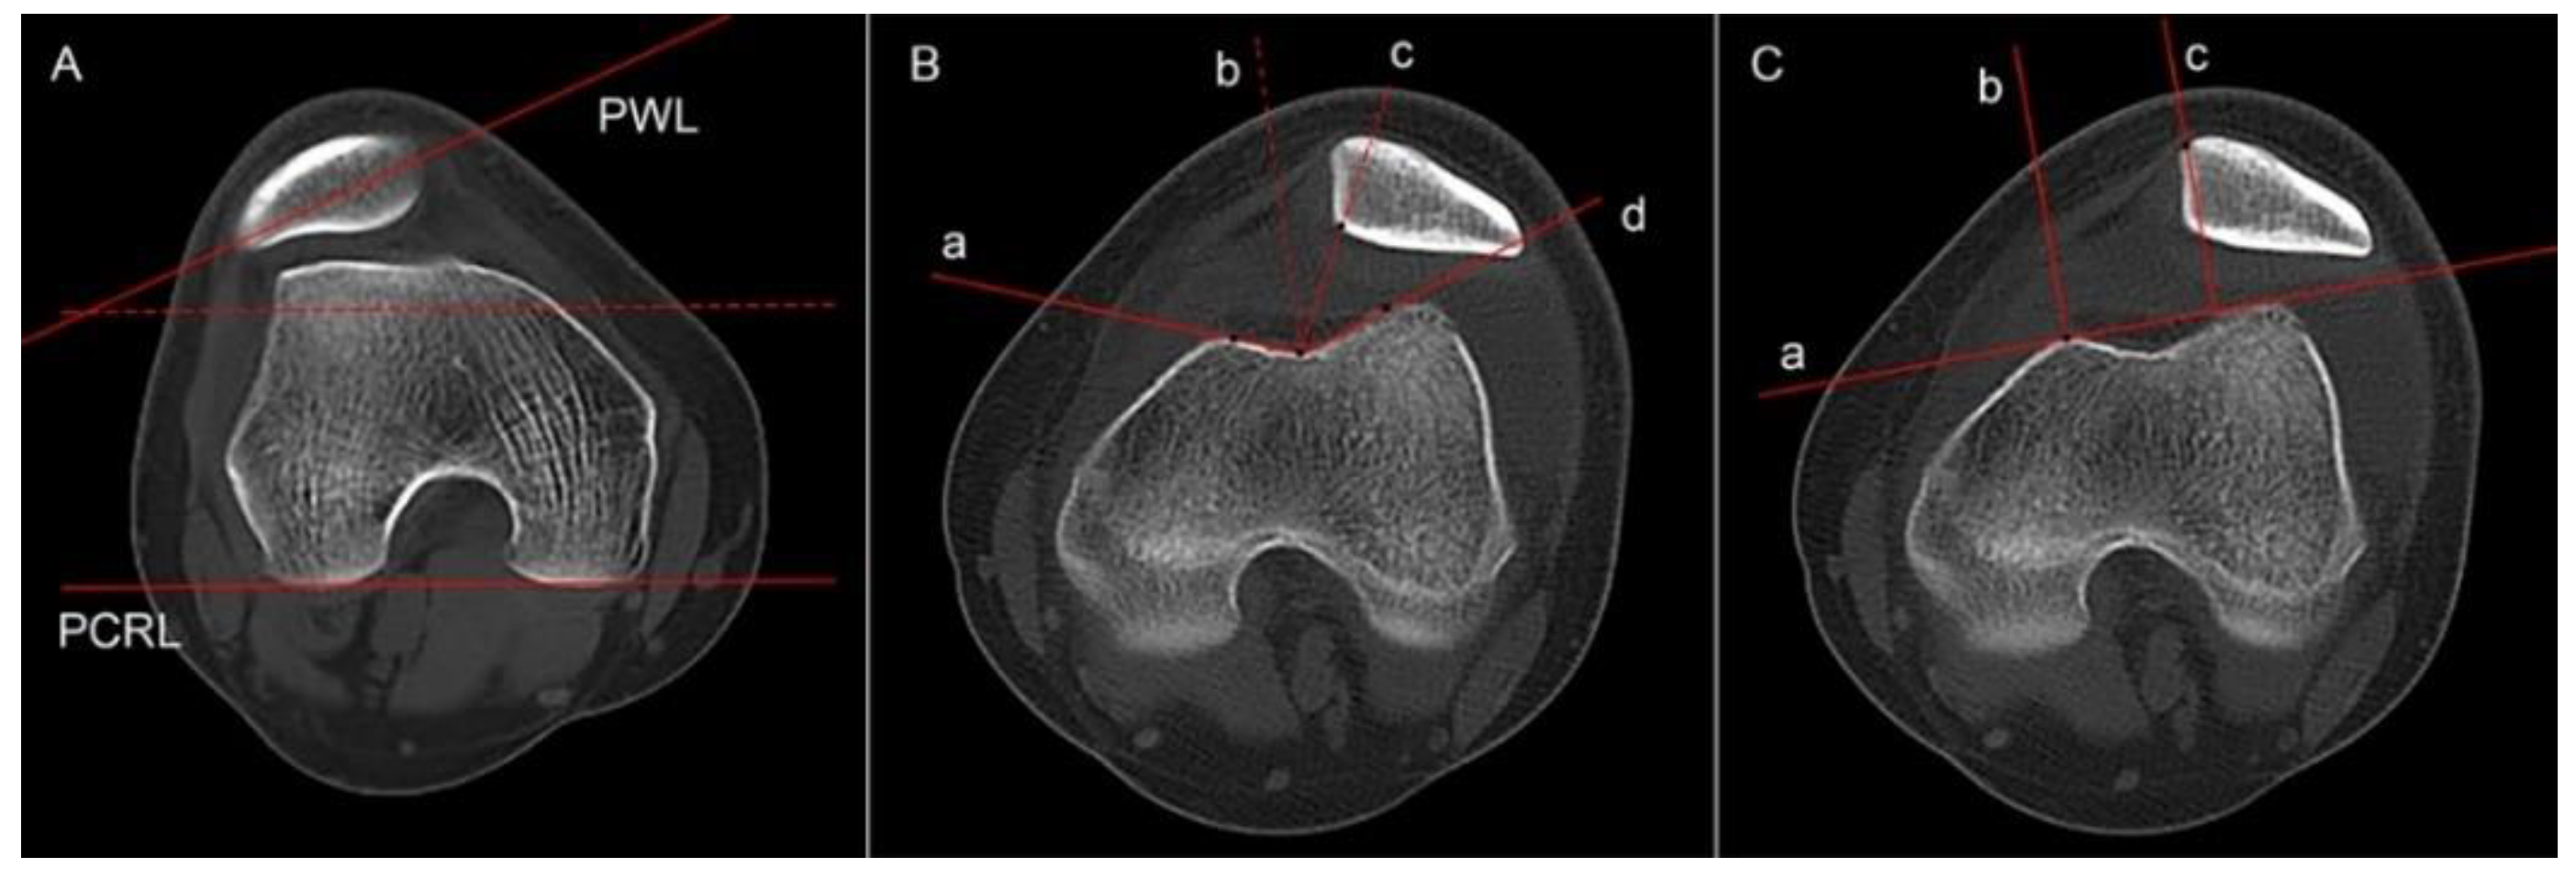

2.3.4. Knee Joint Rotation and Tibial Torsion